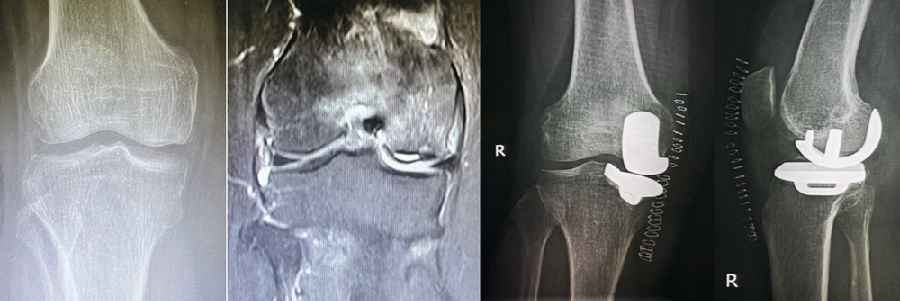

病例3:男,70岁,主诉右膝关节疼痛1年余。查体右膝无肿胀畸形,膝活动度0-120°,内侧间隙压痛。

已经累及44%的股骨内侧髁病变,半月板轻度突出,内侧后角水平撕裂

MRI上深度>20mm

治疗选择保守还是手术?

保守治疗4个月后复查

保守治疗后效果欠佳,坏死范围扩大、塌陷

翻修手术选择截骨矫形还是单髁置换?

最终选择截骨矫形

术后1年1个月

术后2年1个月拆钉

内侧半月板突出未见明显进展